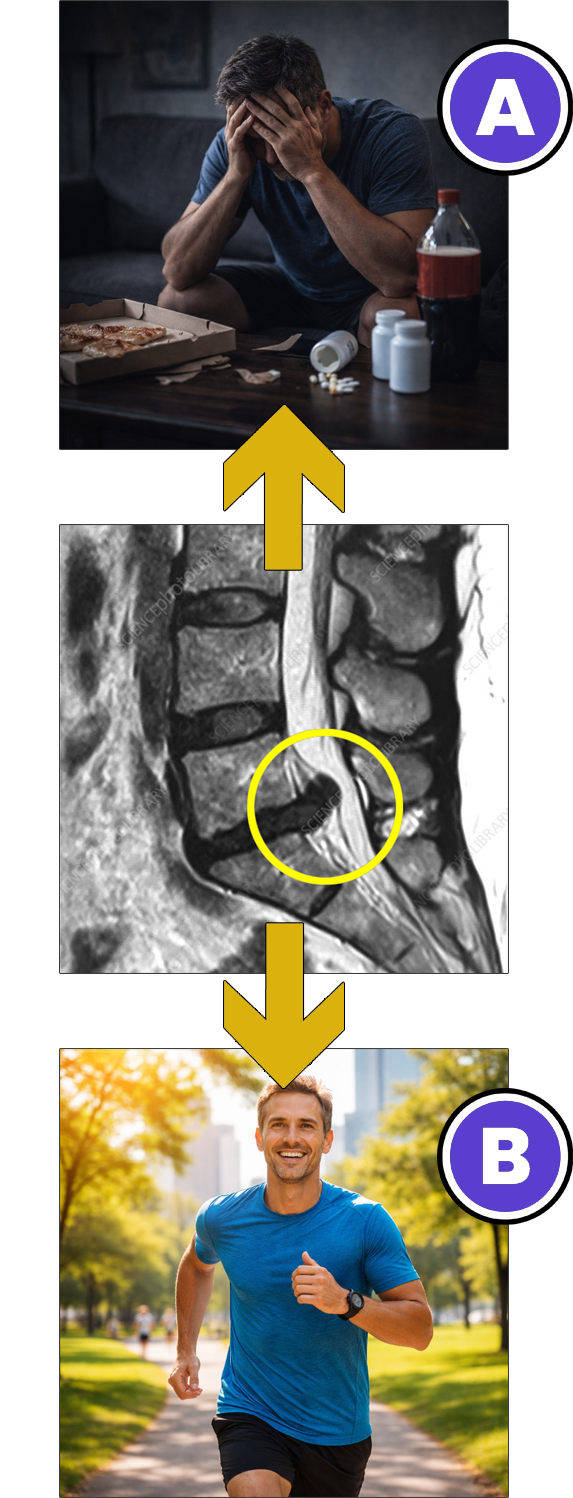

En cuadros crónicos, lo que explica el dolor es siempre lo que sale en la resonancia magnética o los estudios de imagen (hernias, protrusiones, estrechamiento del canal, listesis, cambios facetarios, escoliosis, etc.).

Lo que muestra la evidencia científica es muy distinto. Si bien los resultados de una resonancia pueden aportar información, en la gran mayoría de los casos (+ 90%) no explican ni justifican las causas reales por las cuales muchas personas sienten y experimentan un dolor que no desaparece

Que para resolver de forma final y definitiva tu cuadro de dolor no tenés que enfocarte únicamente en las "lesiones" o patologías mecánicas que salieron en tus estudios de imagen.